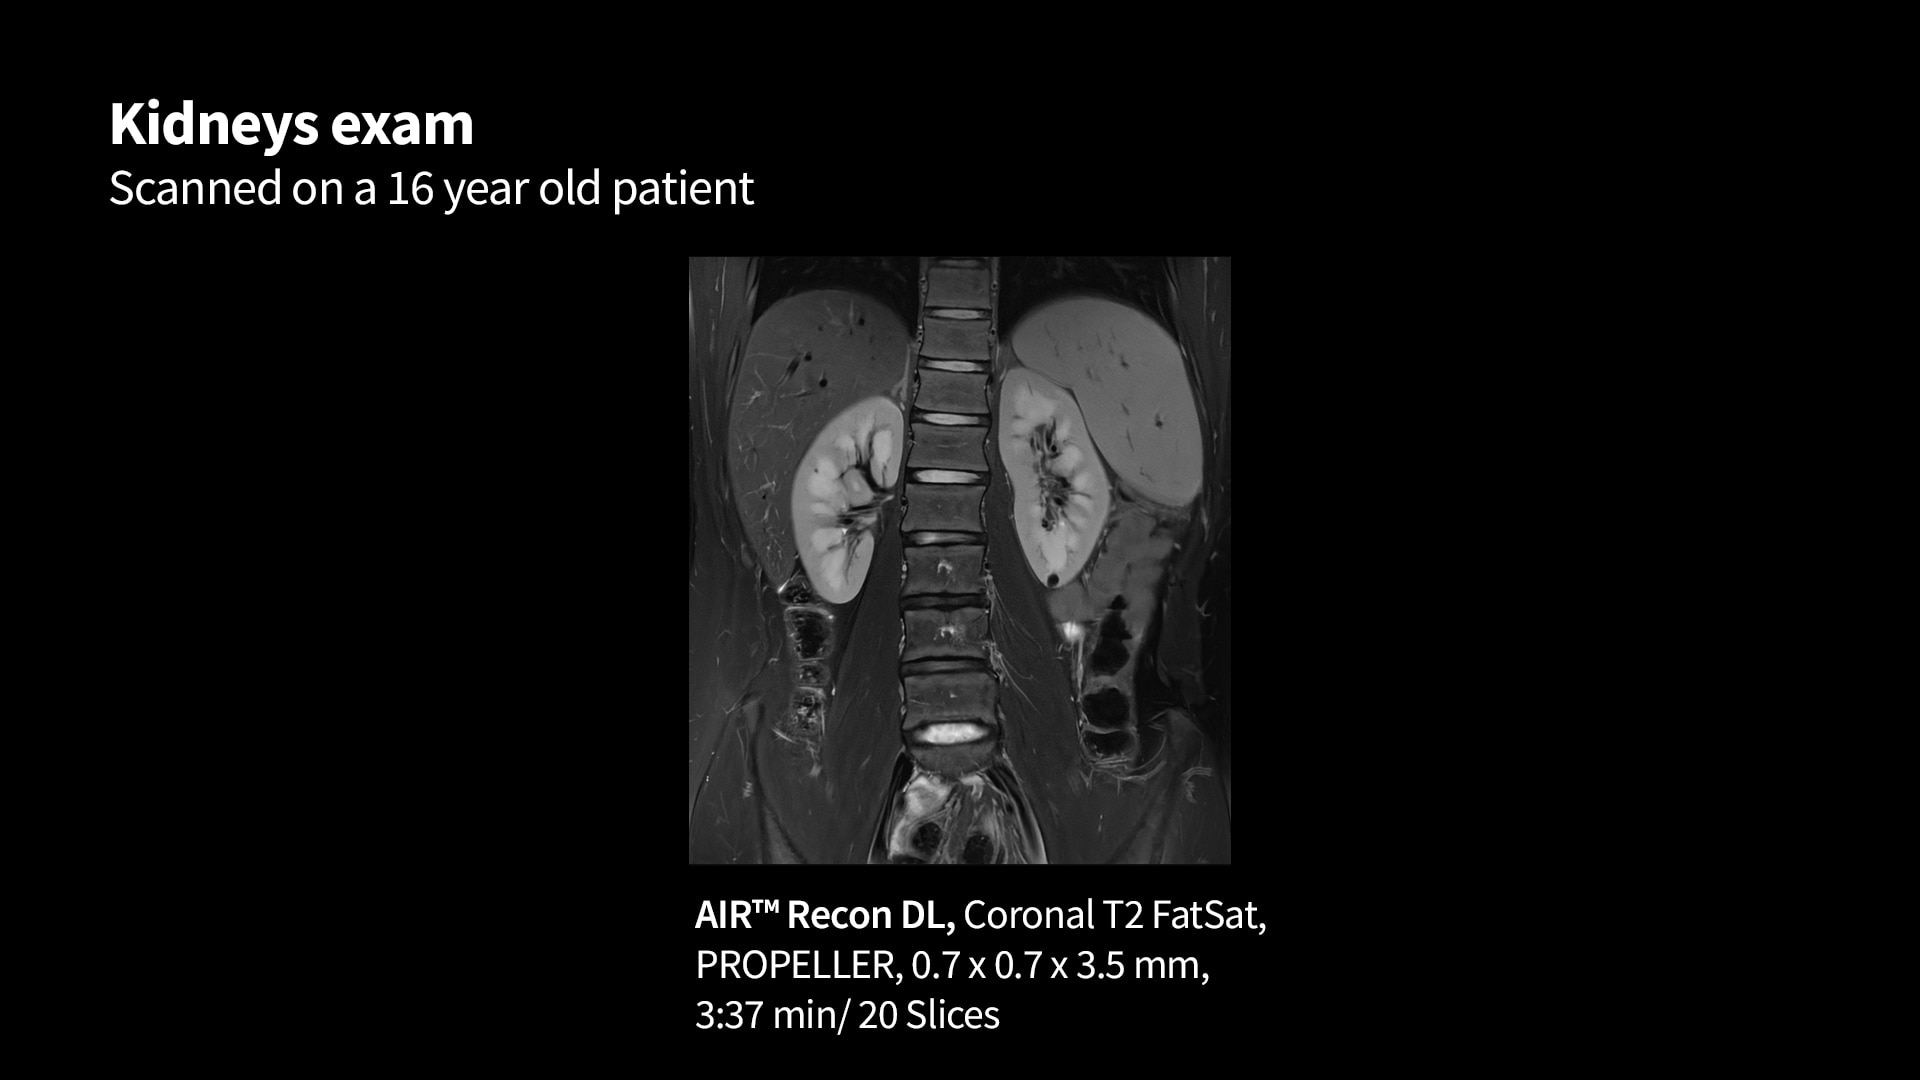

MR image reconstruction with AIR Recon DL

Evolve your MRI scanner's capabilities: experience exceptional image quality without compromising scan time.